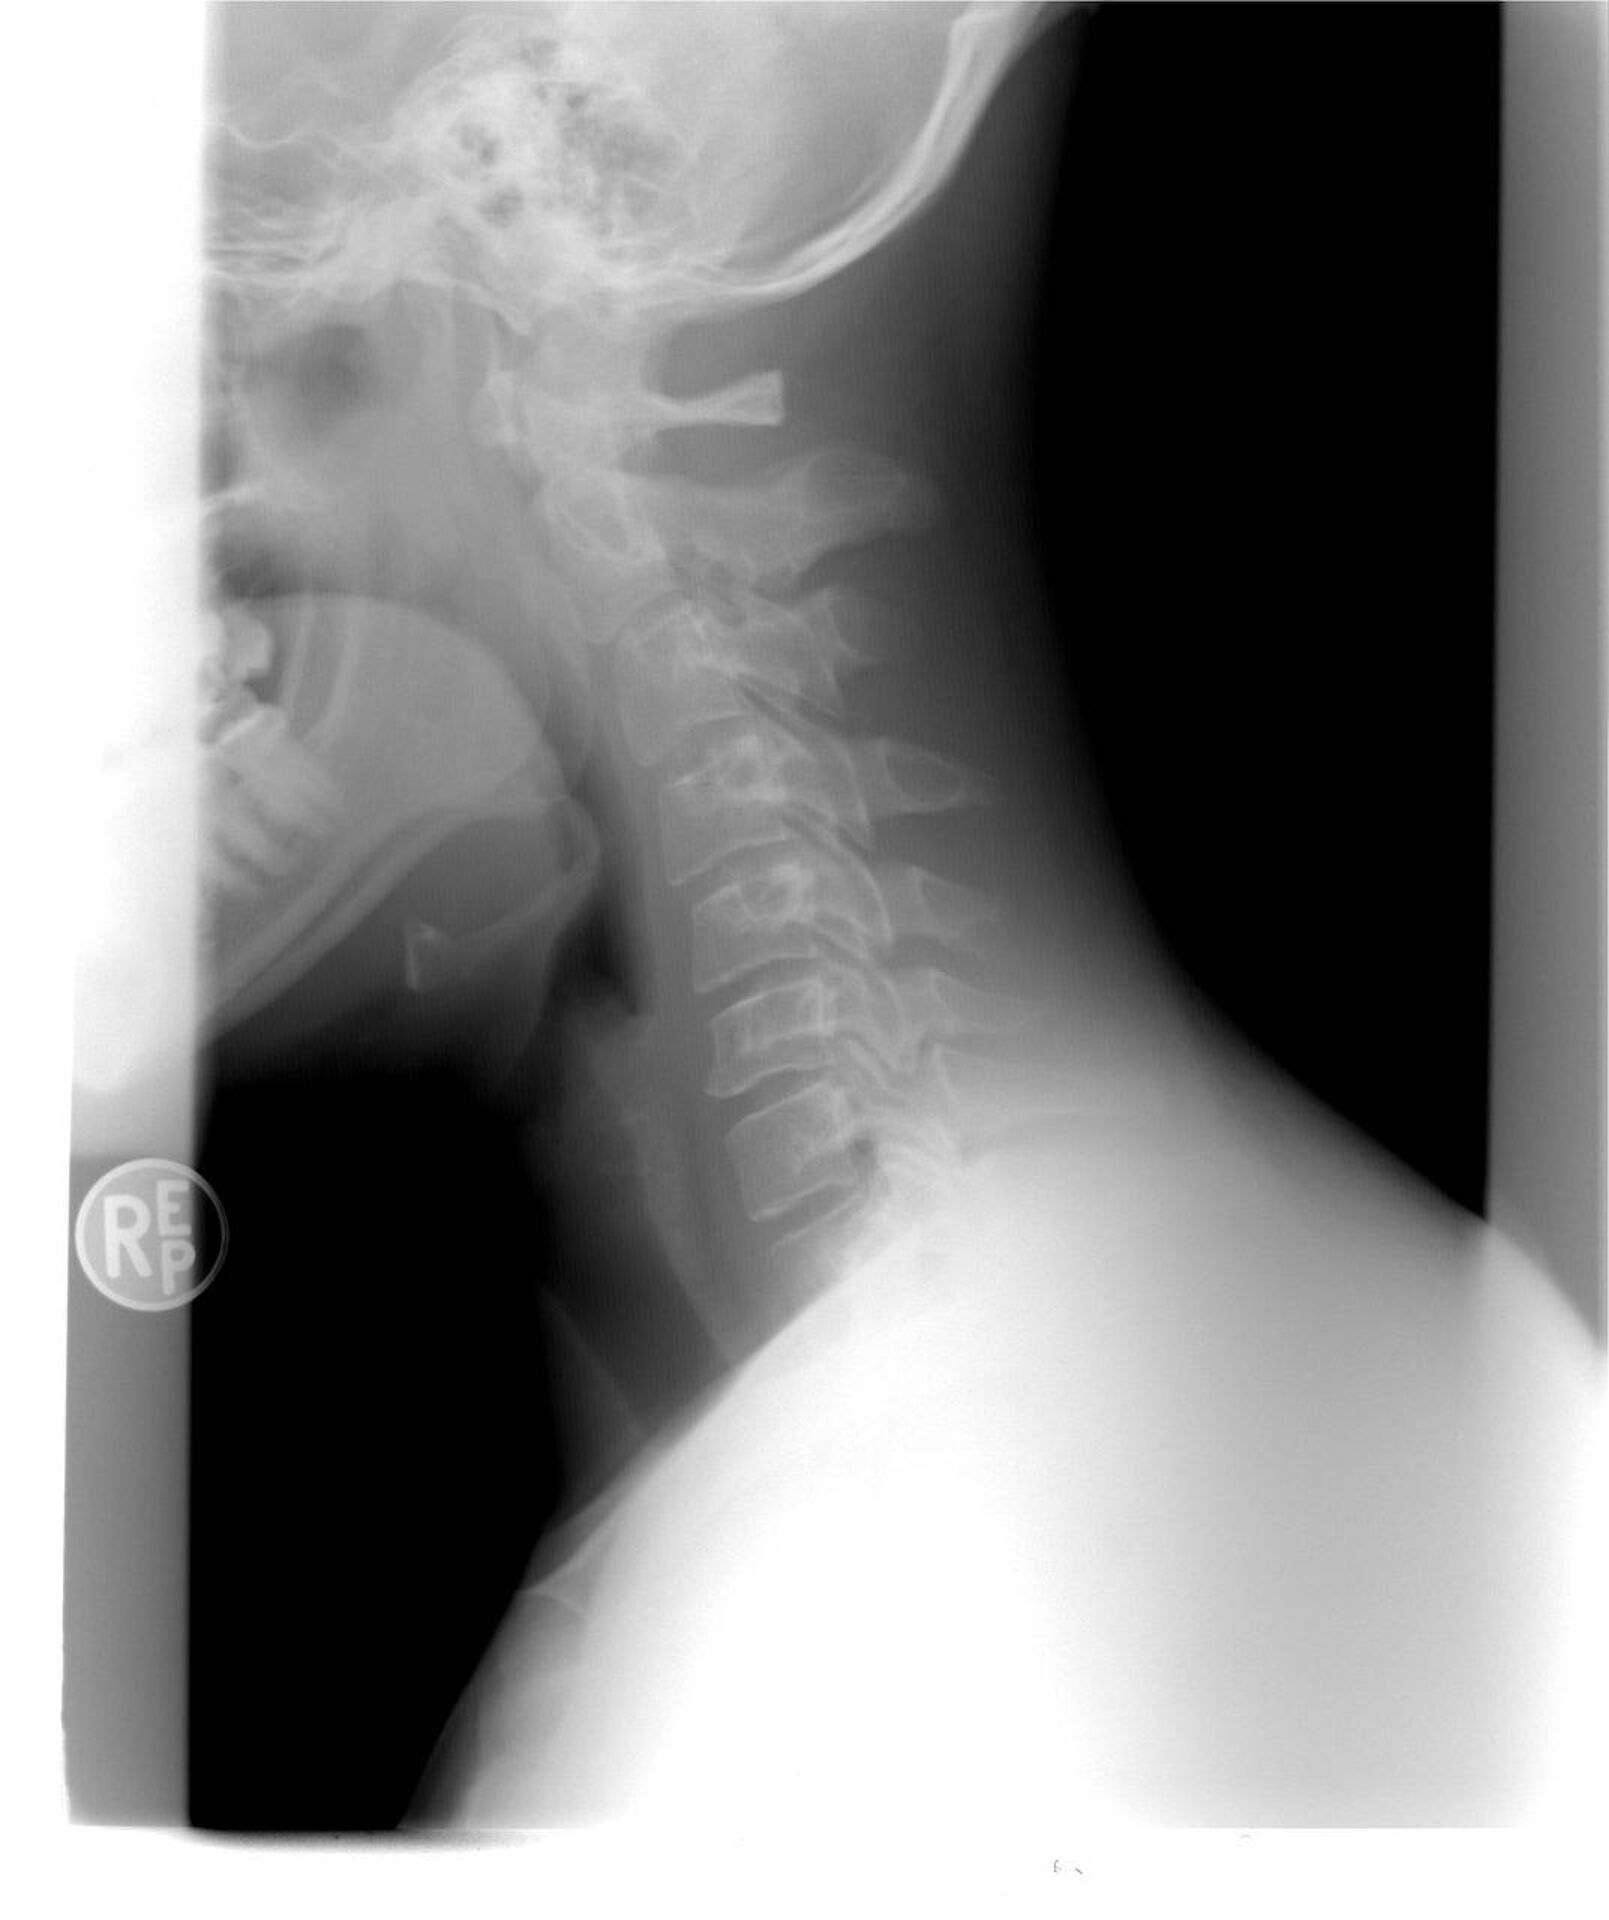

13.425,00 euros alloués à une victime d’accident de la route en voiture ayant subi une entorse cervicale dite aussi coup du lapin à Marseille en indemnisation de son dommage corporel et psychique

Par procès-verbal d’accord transactionnel en date du 25 mai 2023, notre cabinet d’avocats a obtenu le versement de la somme de 13.425,00 euros à une victime d’accident de la route en voiture à Marseille, ayant subi une entorse cervicale, dite aussi coup du lapin en tenant compte des séquelles psychologiques.

Les séquelles au niveau du rachis cervical ont été évaluées à 2 % et il a été demandé à un sapiteur spécialisé en matière psychiatrique d’évaluer les séquelles psychologiques, qui ont été estimées à 3%. Au total, le taux de DFP a été évalué à 5 %.